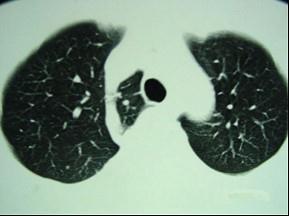

男,40岁,CT检查如图,最可能的诊断为 ( )A、右上肺占位B、右上肺奇叶形成C、右上肺陈旧性结核灶D、右上肺不张E、右上肺纤维化

问题 男,40岁,CT检查如图,最可能的诊断为 ( )

选项 A、右上肺占位 B、右上肺奇叶形成 C、右上肺陈旧性结核灶 D、右上肺不张 E、右上肺纤维化

答案 B